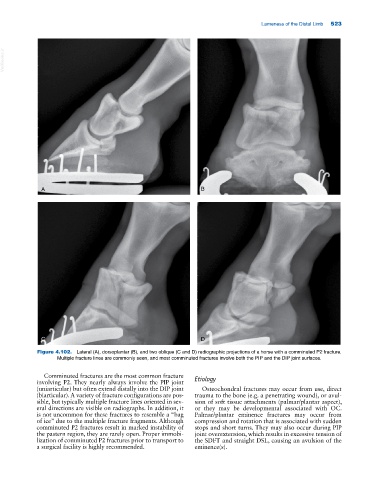

Figure 4.102. Lateral (A), dorsoplantar (B), and two oblique (C and D) radiographic projections of a horse with a comminuted P2 fracture.

Multiple fracture lines are commonly seen, and most comminuted fractures involve both the PIP and the DIP joint surfaces.

Comminuted fractures are the most common fracture

involving P2. They nearly always involve the PIP joint Etiology

(uniarticular) but often extend distally into the DIP joint Osteochondral fractures may occur from use, direct

(biarticular). A variety of fracture configurations are pos- trauma to the bone (e.g. a penetrating wound), or avul-

sible, but typically multiple fracture lines oriented in sev- sion of soft tissue attachments (palmar/plantar aspect),

eral directions are visible on radiographs. In addition, it or they may be developmental associated with OC.

is not uncommon for these fractures to resemble a “bag Palmar/plantar eminence fractures may occur from

of ice” due to the multiple fracture fragments. Although compression and rotation that is associated with sudden

comminuted P2 fractures result in marked instability of stops and short turns. They may also occur during PIP

the pastern region, they are rarely open. Proper immobi- joint overextension, which results in excessive tension of

lization of comminuted P2 fractures prior to transport to the SDFT and straight DSL, causing an avulsion of the

a surgical facility is highly recommended. eminence(s).